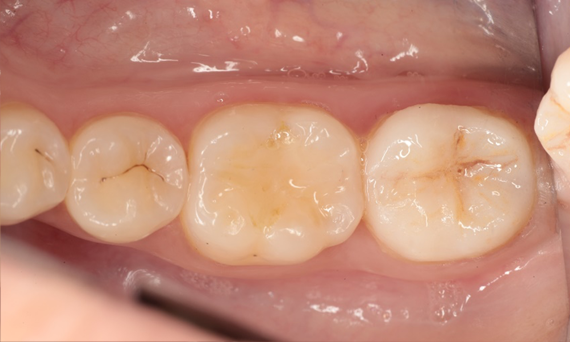

Restoration of MIH teeth with CEREC Tessera

A CEREC Tessera crown

Initial situation of the patient:

The patient presented with increasing temperature sensitivity at her six-year molars. The anamnesis did not reveal any evidence of a drug-associated or disease-associated enamel malformation. The mother’s pregnancy was without complications. Clinical examination revealed extensive substance loss and hypomineralised enamel encompassing the entire clinical crowns of teeth 16 and 26. Furthermore, the left central incisor and both mandibular first molars were affected by hypomineralisations. Tooth 21 had no cavitation and showed no hypersensitivity. The lower first molars had small cavitations with hypersensitivity. Based on these findings diagnosis was molar-incisor-hypomineralisation (MIH). According to the MIH-Treatment-Need-Index [Bekes & Steffen 2016] teeth 16 and 26 were assigned to Score 4c requiring full crown coverage. Tooth 21 was assigned to Score 1 and was left as it was at the request of the mother and the patient herself. Teeth 36 and 46 were assigned Score 4b and were restored with direct composite restorations.

At this point, the maxillary molars were not yet fully erupted. Therefore, these teeth were initially restored with direct composite restorations to await complete tooth eruption. At the age of 11, tooth 16 and 26 had erupted completely allowing for full crown restorations.

Dr. Sebastian Soliman

Würzburg, Germany